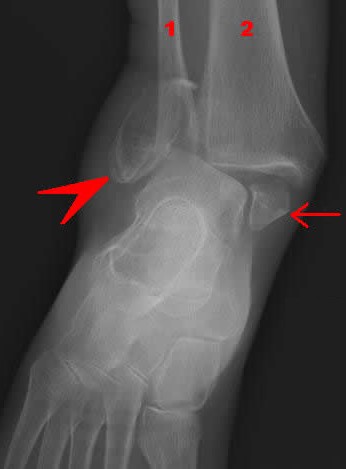

Dislocation/Luxation Complications - Dislocations Accompanied by Fractures

Dislocations often occur with and many times because of fractures of the joint's bone. When the socket in a joint becomes damaged by a fracture, the bone can more easily slip out of place. It is likely that some of the dislocations that surgeons treated during this time were actually accompanied by small fractures, but since X-rays were

Fracture of the Fibula (1) and Tibia (2) with Dislocation of the

Medial

Malleolas (arrow) and Lateral Malleolas (arrowhead) Bones

still centuries away, no one knew it. As a result, they extended dislocations caused by fractures which would have been painful as well as potentially damaging to the already broken bone.